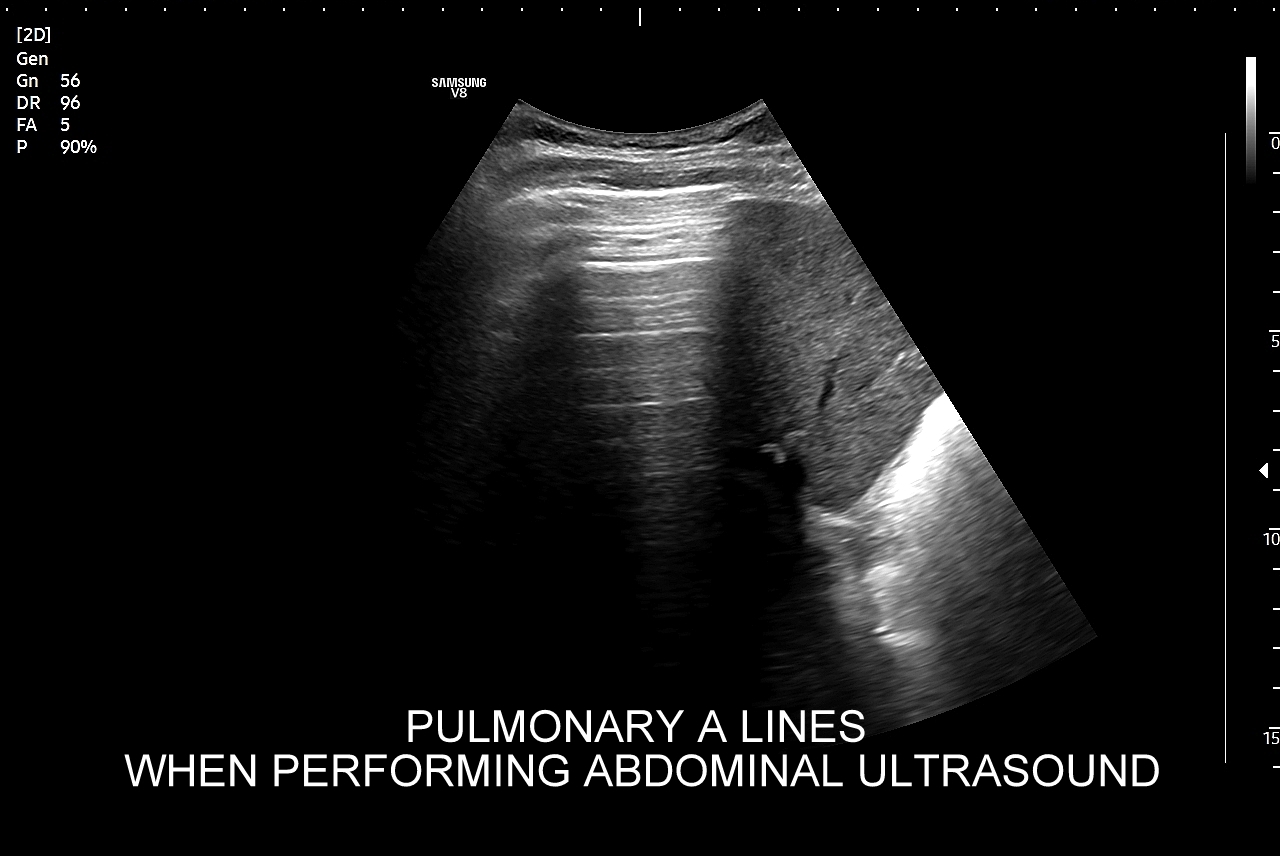

Ultrasonografia płuc oparta jest o fizykę fal akustycznych. Wychwytuje zarówno schorzenia lokalizujące się w zewnętrznych partiach płuc oraz w jamach opłucnowych w postaci realnego obrazu, ale także wykazuje istotne diagnostycznie informacje z głębszych partii narządu na podstawie specyficznych artefaktów generowanych przez patologie wewnątrz płuca.

Diagnostyka ultrasonograficzna łącznie z klasycznym RTG oraz tomografią klatki piersiowej (TK) stanowią podstawową triadę nieinwazyjnych badań obrazowych dolnych dróg oddechowych, w tym płuc. Przykładem badania inwazyjnego jest z kolei bronchoskopia, a przykładem badania czynnościowego spirometria. Wymienione metody diagnostyczne są procedurami, które w ramach oceny układu oddechowego nawzajem się uzupełniają. Zaletą USG płuc jest to, iż można je wykonać szybko i sprawnie podczas wizyty ambulatoryjnej w lekarskim gabinecie internistycznym bądź pediatrycznym albo przyłóżkowo w warunkach szpitalnych. Oznacza to znaczne przyspieszenie procesu diagnostycznego i terapeutycznego, a przeprowadzenie badania USG płuc może w pewnych sytuacjach uratować nawet życie pacjentowi.